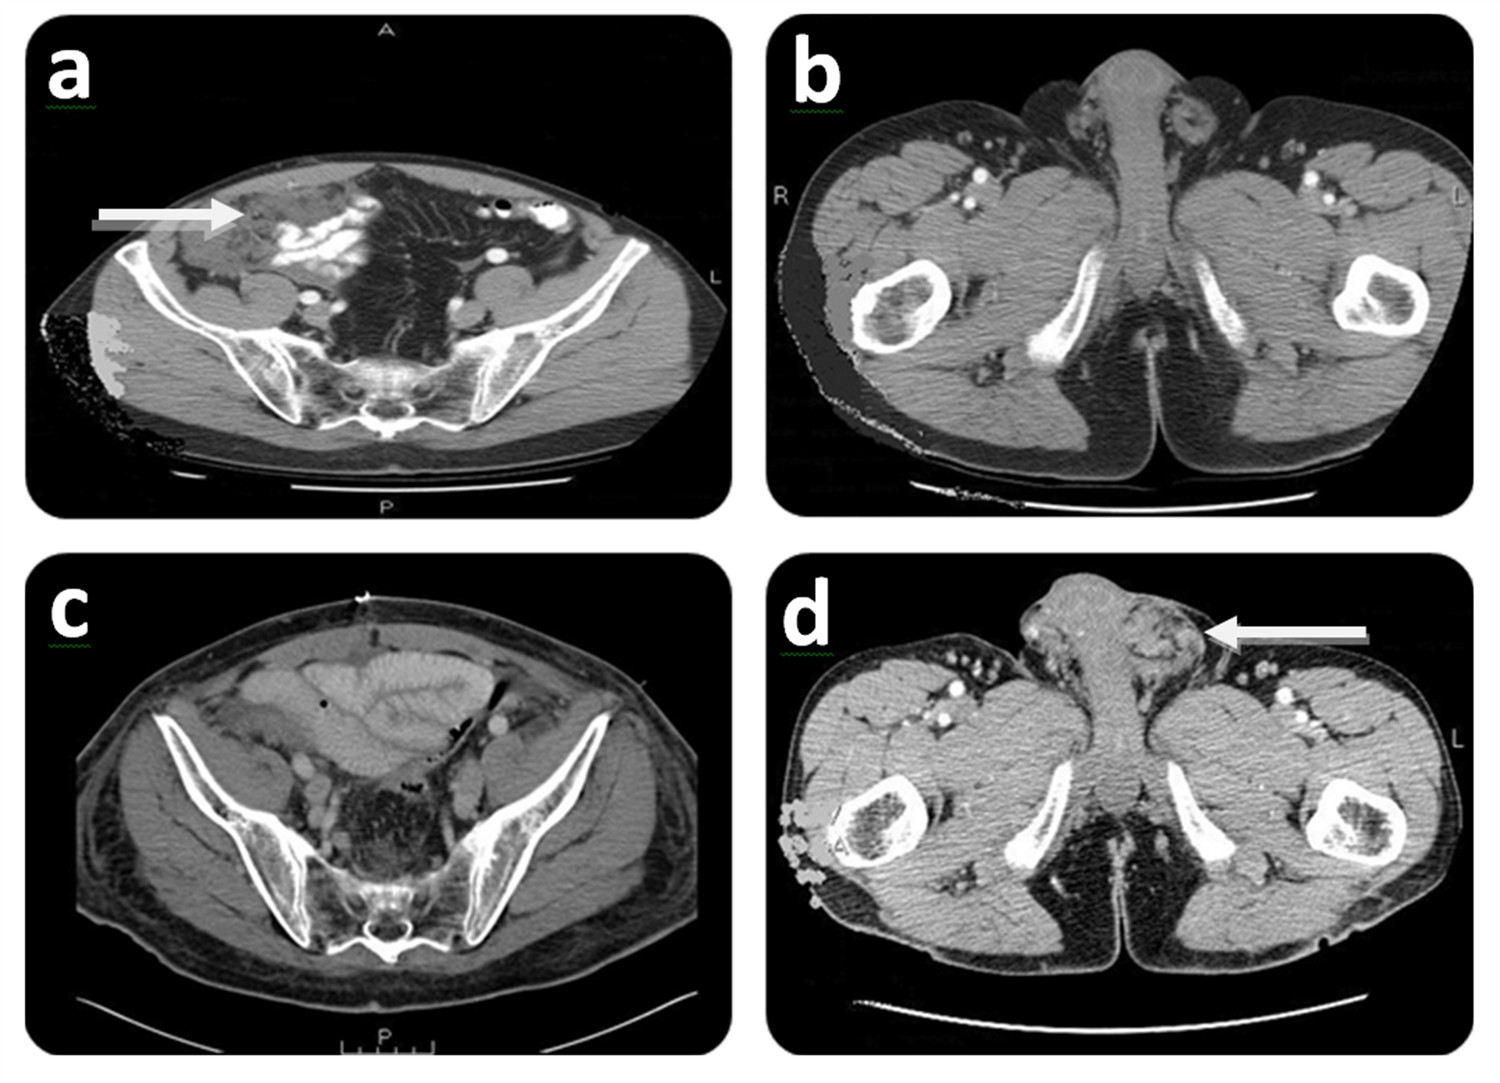

Figure 3.

Initial and follow-up CT scan findings of Case # 2. Preoperative: A) CT scan shows right lower abdominal mass (white arrow) at initial CRS/HIPEC. A: Anterior; P: Posterior. B) CT scan shows no groin involvement at initial CRS/HIPEC. R: Right side; L: Left side. Postoperative (7 months after CRS/HIPEC): C) CT scan shows no evidence of disease at time of scrotal recurrence. P: Posterior. D) CT scan showing left scrotal mass (white arrow). L: Left side.

Five months after the herniorrhaphy the patient was referred to our Institution with a complaint of right lower abdominal discomfort. Further evaluation with a CT scan showed diffuse peritoneal metastases (Fig. 3A). No groin disease was found on physical examination or CT scan (Fig. 3B). Three weeks later, the patient underwent a CRS/HIPEC for DPAM. The pre/post surgical PCI was 36/0 and a CC-0 was achieved. Hyperthermic intraperitoneal chemotherapy (closed technique) was carried out by using 40 mg of Mitomycin-C for 90 min (30 mg given at time 0 and 10 mg 30 min later) with inflow temperature maintained at 43° C an outflow temperature of 41-42° C. Seven months later, on follow up, the patient presented with left groin discomfort and a scrotal mass. A CT scan identified no evidence of intra-abdominal disease (Fig. 3C), and a left scrotal mass (Fig. 3D). Fine-needle aspiration determined the existence of mucin in the left scrotum. Two months later the patient had CRS including left orchiectomy, removal of in-situ Prolene(r) mesh, HCS (Fig. 1) and subsequent repair of inguinal defect with Prolene(r) mesh. Complete cytoreduction was achieved at this stage. The patient was discharged on post-operative day 3 without complication. On follow up, the patient is considered NED at 57 months after his initial CRS/HIPEC and 32 months post CRS/HCS.